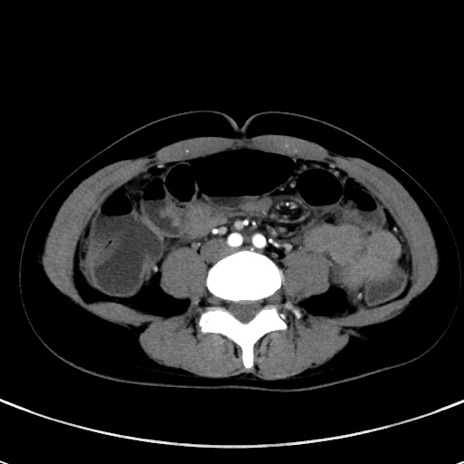

症例17(横断像)

【症例】20歳代女性

【主訴】嘔吐、下腹部痛

【現病歴】昨日夕食後に嘔吐し下腹部痛が出現。本日になっても嘔吐持続し改善しないため来院。

【身体所見】意識清明、BT 37.2℃、BP 108/67mmHg、腹部:平坦、やや硬、下腹部正中から右にかけて圧痛あり、反跳痛軽度あり、tapping pain(+)。

【データ】WBC 13600、CRP 14.94